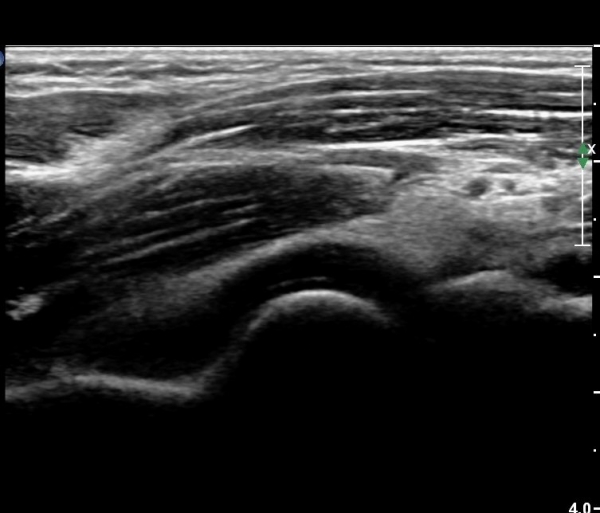

ÆÈ²ÞÄ¡ µÚÂÊ Á¾´Ü¸é°Ë»ç¿Í Ⱦ´Ü¸é°Ë»ç¿¡¼­ ÁֵοÍ(olecranon fossa)¿¡ ¼ö¾×Àú·ù°¡ °üÂûµÊ(»çÁø 1, 2)